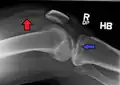

A severe tibial plateau fracture with an associated fibular head fracture

Fractures of the tibial plateau are caused by a varus (inwardly angulating) or valgus (outwardly angulating) force combined with axial loading or weight bearing on knee. The classically described situation in which this occurs is from a car striking a pedestrian's fixed knee (bumper fracture). A bumper fracture is usually a fracture of the lateral tibial plateau, caused by a forced valgus movement. This causes the lateral part of the distal femur and the lateral tibial plateau to come into contact, compressing the tibial plateau and causing the tibia to fracture. The name of the injury is because it was described as being caused by the impact of a car bumper on the lateral side of the knee while the foot is planted on the ground, although this mechanism is only seen in about 25% of tibial plateau fractures.[5] The term "bumper fracture" was coined in 1929 by Cotton and Berg.[6] Fracture of the neck of the fibula may also be found, and associated injury to the medial collateral ligament or cruciate ligaments occurs in about 10% of cases.[7][8]

This is a medial tibial plateau fracture with a split or depressed component. It is usually the result of a high energy injury and involves a varus force with axial loading at the knee. Represent 10% of all tibial plateau fractures. There is high risk of damage to the popliteal artery and peroneal nerve and therefore carry a worse prognosis. May include distraction injuries to lateral collateral ligament, fibular dislocation/fracture, posterolateral corner.